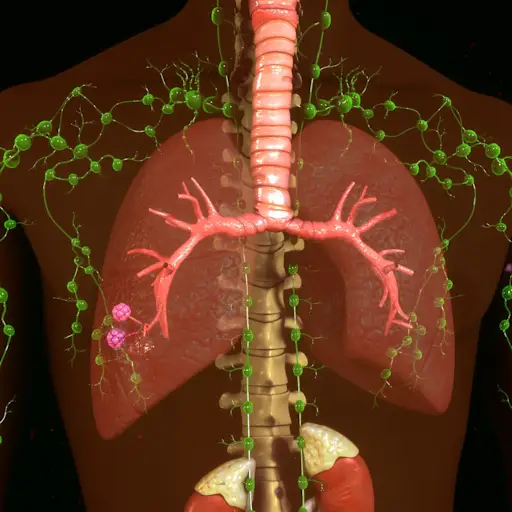

“转移性肾癌会引起代谢问题,荷尔蒙问题,它还会扩散到心脏血管,”丹尼尔·乔治医学博士说,他是位于北卡罗来纳州达勒姆的杜克大学医疗保健中心的医学肿瘤学家和教授。这是因为肾癌很容易通过血液和淋巴系统扩散到大脑、心脏、肺、骨骼和肝脏。乔治博士说,你体内癌症的数量或肿瘤负担,决定了肾癌是否会导致这些区域的其他情况或并发症的发展。